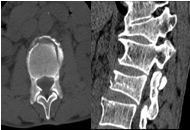

微创骨科采用经皮椎体成形术治愈了89岁老奶奶腰椎骨折(微创骨科:任杰)

刘奶奶,89岁,因上厕所摔伤腰痛,翻身困难,不敢坐起和下地行走,疼痛难忍4天,卧床没有好转,来我院微创骨科就诊,经检查腰椎3压痛、叩痛,拍x光片和核磁确诊腰椎3骨折。因骨质增生腰椎麻醉困难,微创骨科任杰主任应 用最先进的微创技术采用局麻下行椎体成形术,术后老人家就感觉疼痛马上减轻了,儿孙都非常高兴,老人不用卧床了,可以下地行走自己上厕所、坐着吃饭。避免了保守治疗需卧床3个月引起的并发症:坠积性肺炎、褥疮、下肢静脉血栓、严重骨质疏松、泌尿系感染和结石等,甚至危及生命。家人感激不尽,老人不用卧床遭罪了,减轻了家人护理负担,不用耽误工作,保证老人正常生活质量,延长了寿命。

随着老龄化社会的到来,骨质疏松性骨折发病率逐年增加。近年来针对骨质疏松性椎体骨折因不能采取有效内固定,而采用了椎体成形术。微创手术—经皮椎体成形术(PercutaneousVertebroplasty,PVP)是指经皮通过椎弓根或椎弓根外向椎体内注入骨水泥以达到增加椎体强度和稳定性,防止塌陷,缓解疼痛,甚至部分恢复椎体高度为目的一种微创脊椎外科技术。

术前

术后